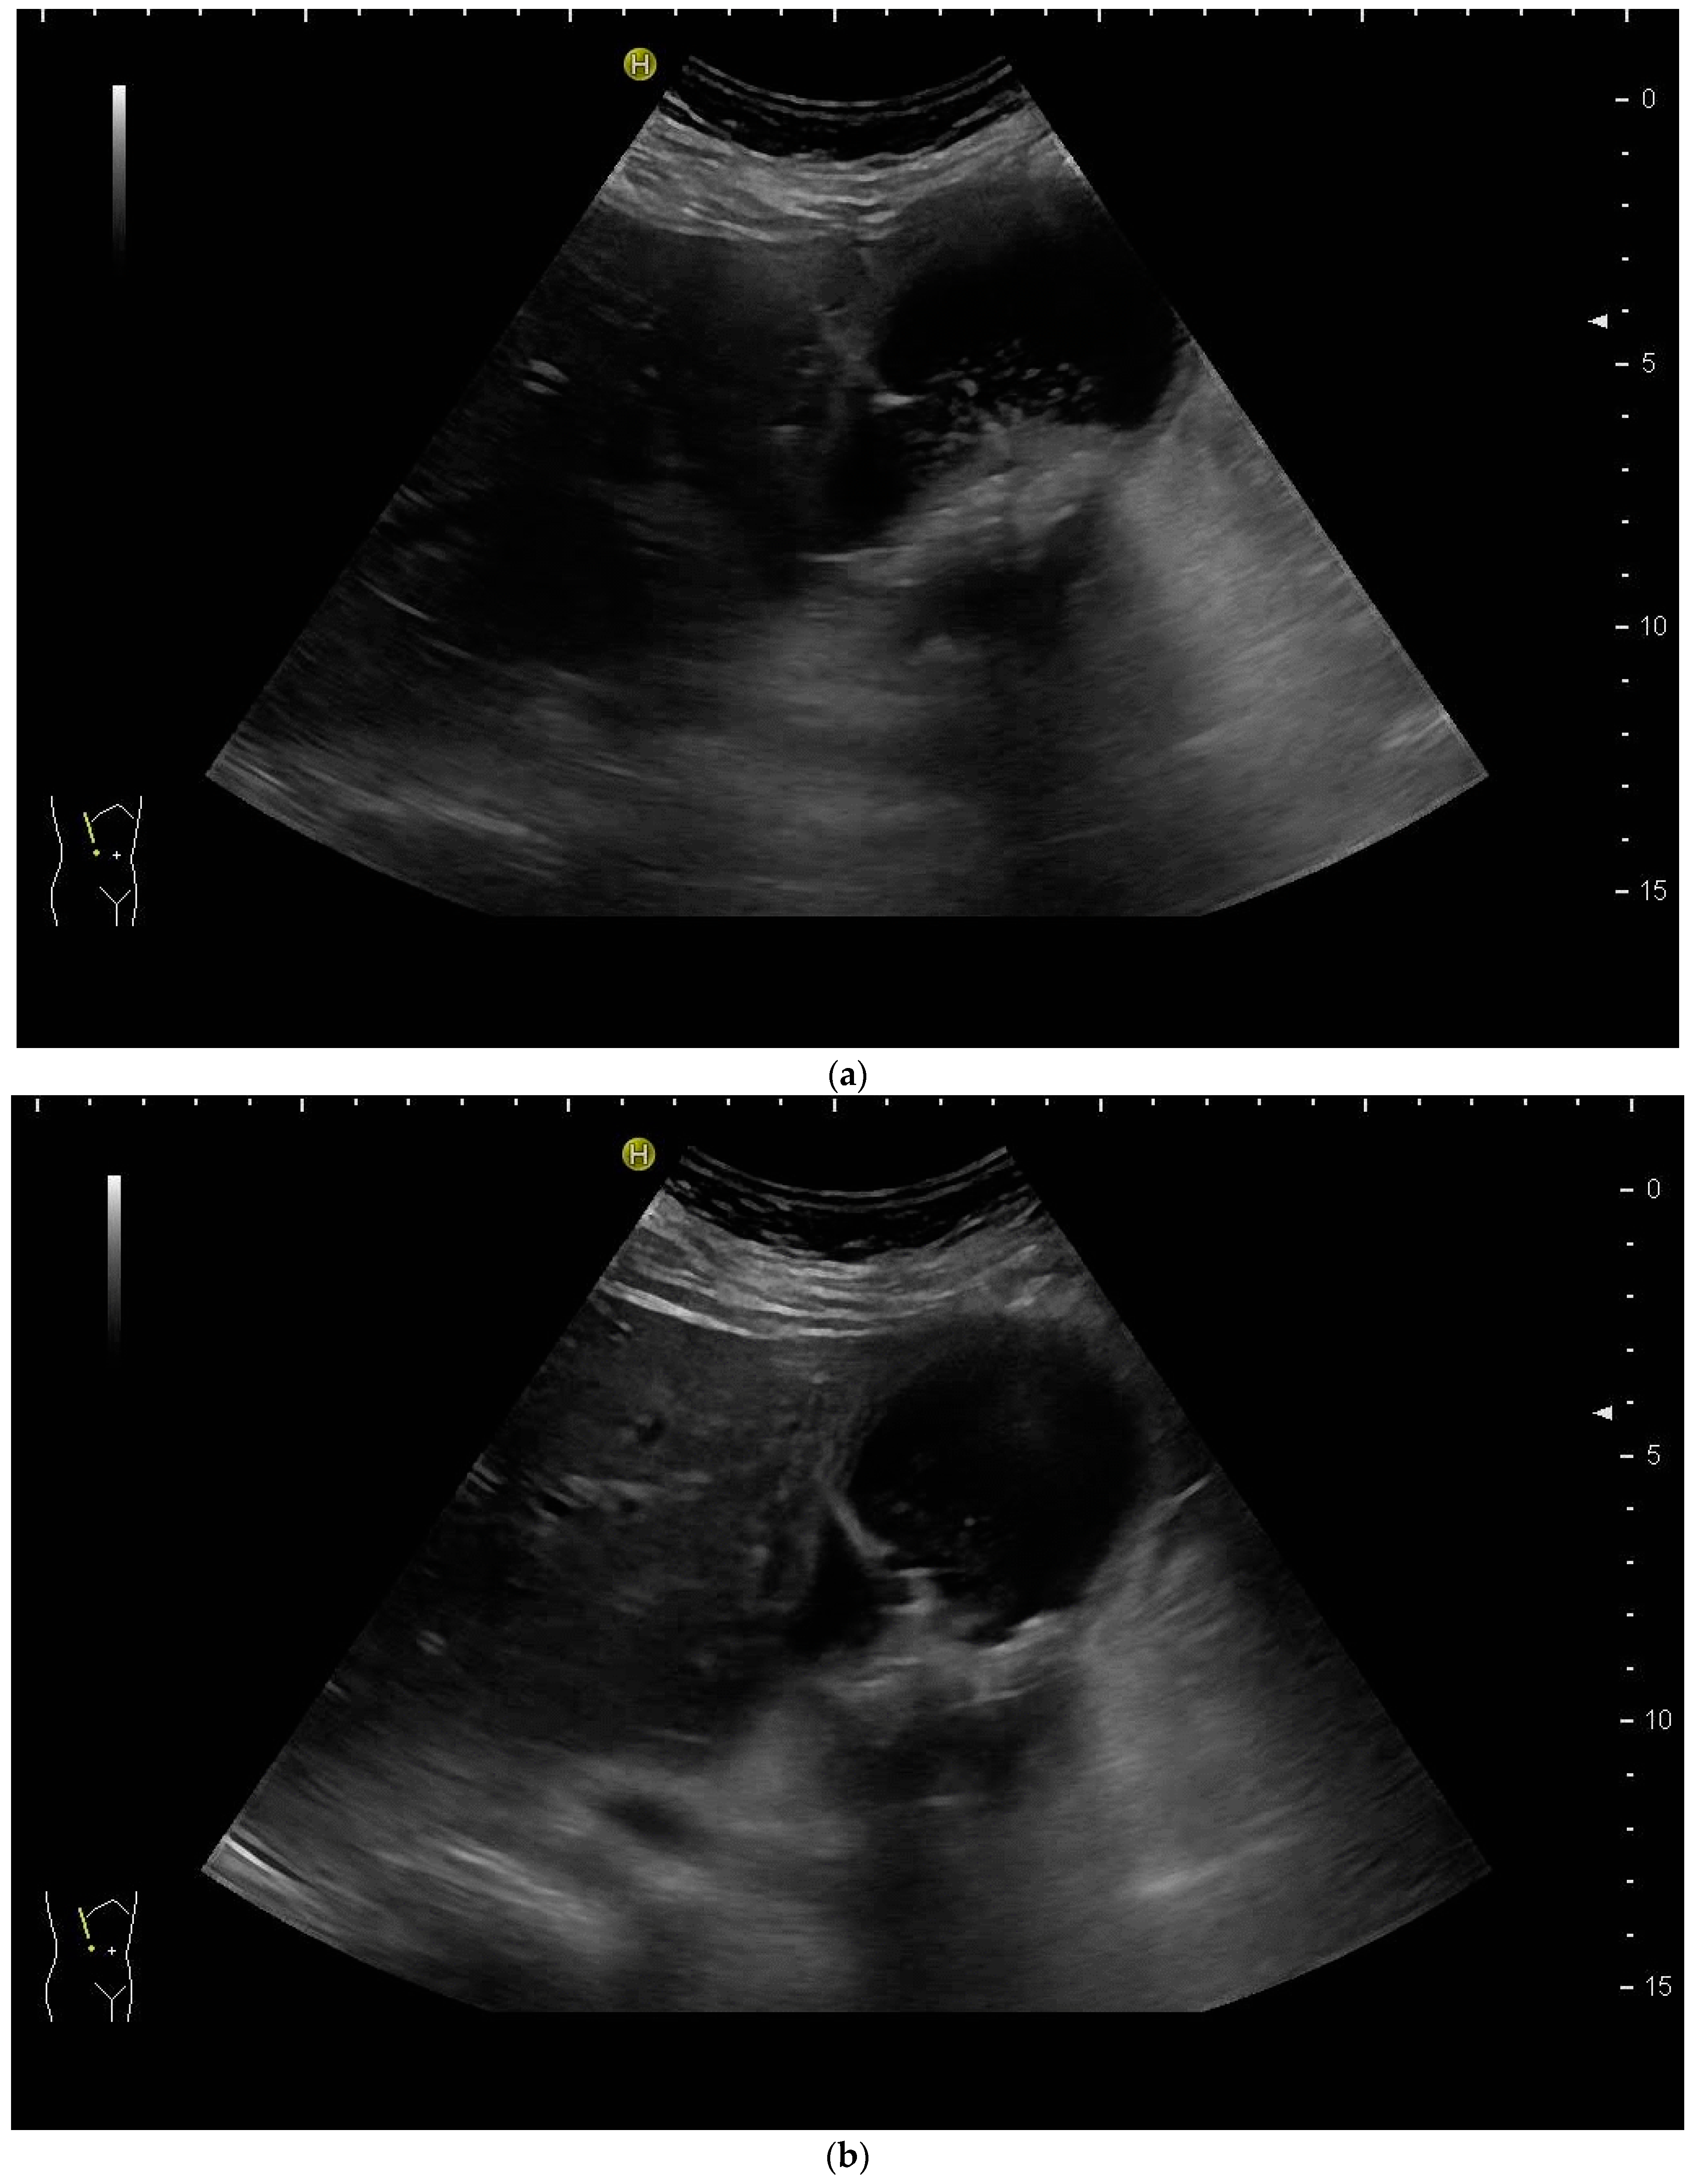

Most authors recommend a transhepatic approach in order to prevent biliary leakage to the abdominal cavity during drainage or after removal of drainage [43,55,56,76,77] (Figure 9).

Figure 9.

(a) Transhepatic puncture of an inflamed gall bladder in the in-plane technique. The Chiba needle is depicted well; (b) A few days later, laparoscopic cholecystectomy was performed. The drainage ran through Segment V of the liver. It was removed without provoking biliary leakage from the liver parenchyma.

The consideration is that a perforation in the hepatic surface of the gallbladder will be covered by the liver tissue after the removal of the drain. However, retrospective analyses comparing the transhepatic route with the transperitoneal (i.e., nontranshepatic) access (Figure 10) report no differences in the complication rates [58,78,79].

Figure 10.

PGBD without passing the liver and using the trocar technique: straightened drainage passes right below the lower liver margin into the gallbladder.

Again, the “in plane” approach is recommended to depict the needle in real time and continuously on its way. This is mandatory because iatrogenic perforation of the posterior gallbladder wall must be avoided. Both the drainage techniques, Seldinger (Figure 11a–c) and trocar (direct puncture, cf. Figure 10), may be used, depending on the physician’s preferences [43,58].

Figure 11.

When using the Seldinger technique, first a Chiba needle is placed in the gallbladder (a), through which a 0.035” guide wire with bended tip is inserted (b). Plastic pigtail drainage (c) is then advanced over the guide wire.